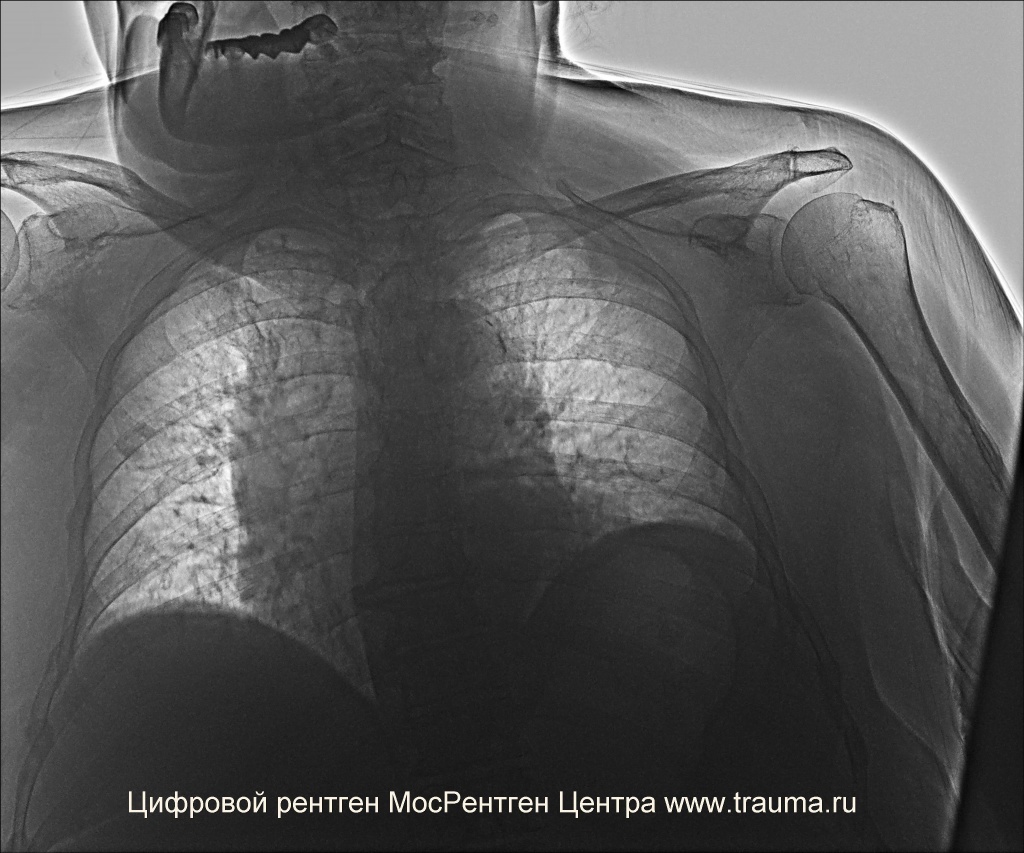

Рентгеновские снимки при врожденной эмфиземе легкого

Раздел: Визуальные уроки